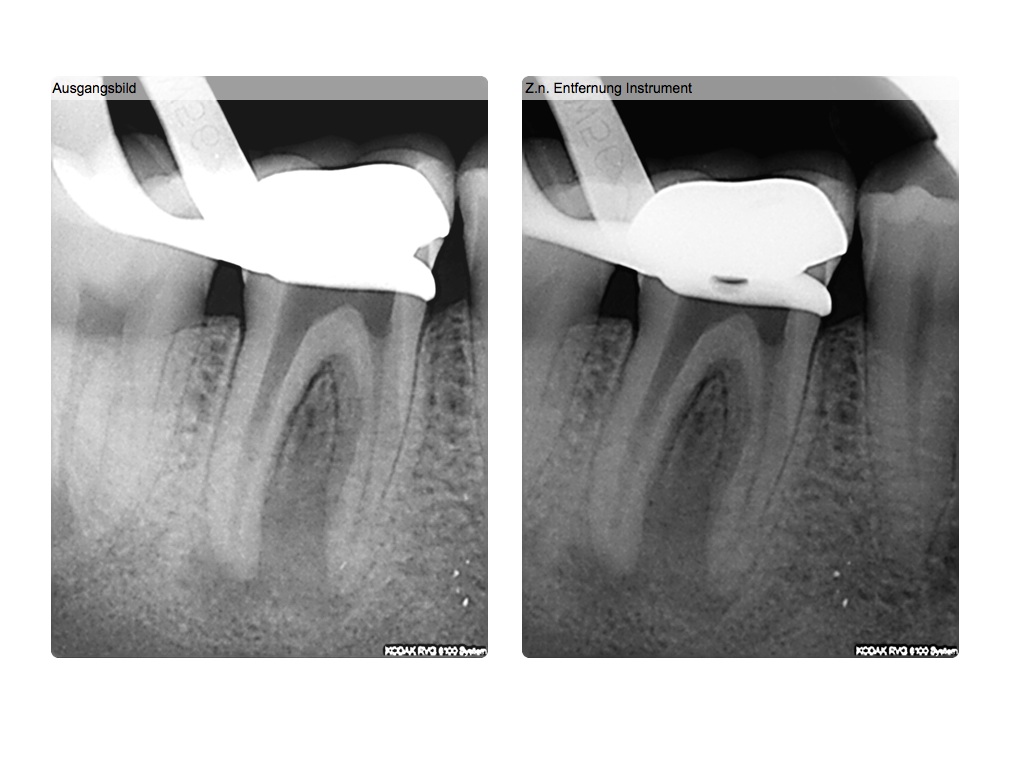

Röntgenbilder lügen…